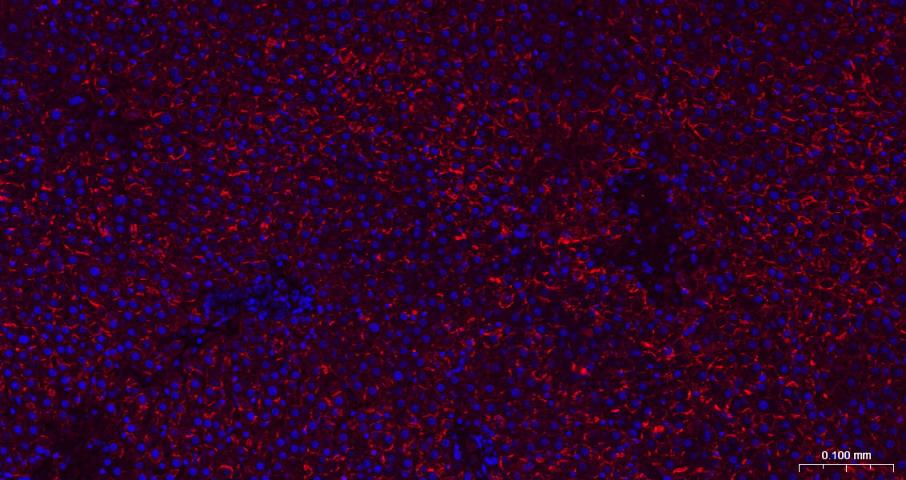

Paraformaldehyde-fixed, paraffin embedded Mouse Liver; Antigen retrieval by boiling in sodium citrate buffer (pH6.0) for 15 min; The section was incubated with N Cadherin Monoclonal Antibody, Unconjugated (bsm-52389R) at 1:200 overnight at 4°C. Followed by conjugated Goat Anti-Rabbit IgG antibody (Red, bs-0295G-BF594), DAPI (blue, C02-04002) was used to stain the cell nuclei.